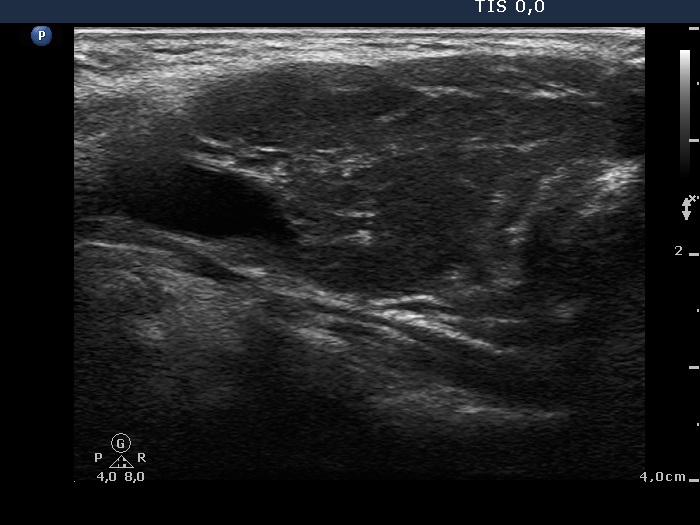

First examination (first and second rows of images):

Clinical presentation: A 33-year-old woman was referred for an evaluation of complaints suggesting hyperthyroidism. The patient was never pregnant.

Palpation: no abnormality.

Results of blood test: TSH undetectable, FT4 31.0 pM/L, aTPO 703 U/mL, TSAb 0.5 U/L (normal value < 1.5).

Ultrasonography: A diffusely hypoechogenic thyroid was found with several discrete lesions. The vascularization was increased.

Cytology was performed from the right lobe.Cytological diagnosis: benign pattern corresponding to hyperthyroidism without any signs of thyroiditis.

Considering the results of investigation, low dose (daily 15 mg) methimazole was administered.